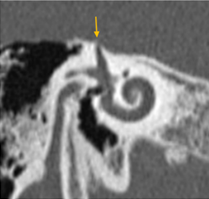

Tamaño del nicho de la ventana oval: Valores de 1,4 mm se toma como límite inferior de la normalidad. Valores menores se asociaban con un riesgo mayor de tener dificultades técnicas durante la cirugía del estribo. Debe descartarse una otosclerosis obliterativa (Fig. 4-5). |

Figura 4. Vista de la ventana oval en un corte coronal del oído medio |

Figura 5. Ventana oval obliterativa de oído derecho en un corte coronal de oído medio |